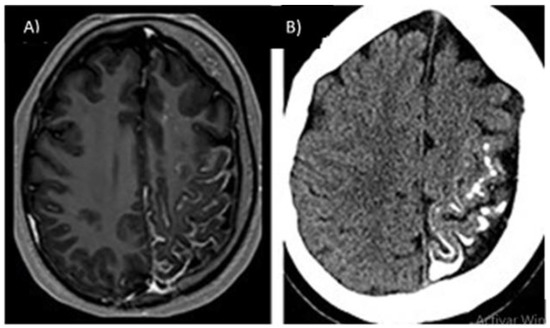

3.3.2. Capillary-Venous Angioma (Sturge–Weber)

- Sebold, A.J.; Day, A.M.; Ewen, J.; Adamek, J.; Byars, A.; Cohen, B.; Kossoff, E.H.; Mizuno, T.; Ryan, M.; Sievers, J.; et al. Sirolimus Treatment in Sturge-Weber Syndrome. Pediatric Neurol. 2021, 115, 29–40. [Google Scholar] [CrossRef]

- Hassanpour, K.; Nourinia, R.; Gerami, E.; Mahmoudi, G.; Esfandiari, H. Ocular Manifestations of the Sturge–Weber Syndrome. J. Ophthalmic Vis. Res. 2021, 16, 415. [Google Scholar] [CrossRef]

- Bianchi, F.; Auricchio, A.M.; Battaglia, D.I.; Chieffo, D.R.P.; Massimi, L. Sturge-Weber Syndrome: An Update on the Relevant Issues for Neurosurgeons. Childs Nerv. Syst. 2020, 36, 2553–2570. [Google Scholar] [CrossRef]

- Zallmann, M.; Leventer, R.J.; Mackay, M.T.; Ditchfield, M.; Bekhor, P.S.; Su, J.C. Screening for Sturge-Weber Syndrome: A State-of-the-Art Review. Pediatr. Dermatol. 2018, 35, 30–42. [Google Scholar] [CrossRef] [Green Version]

- Kasinathan, A.; Saini, A.G.; Vyas, S.; Singhi, P. Angiodysplastic Sturge Weber Syndrome. BMJ Case Rep. 2018, 2018, bcr-2017-222869. [Google Scholar]

- Day, A.M.; McCulloch, C.E.; Hammill, A.M.; Juhász, C.; Lo, W.D.; Pinto, A.L.; Miles, D.K.; Fisher, B.J.; Ball, K.L.; Wilfong, A.A.; et al. Physical and Family History Variables Associated With Neurological and Cognitive Development in Sturge-Weber Syndrome. Pediatric Neurol. 2019, 96, 30–36. [Google Scholar] [CrossRef]

- Maraña Pérez, A.I.; Ruiz-Falcó Rojas, M.L.; Puertas Martín, V.; Domínguez Carral, J.; Carreras Sáez, I.; Duat Rodríguez, A.; Sánchez González, V. Análisis Del Síndrome de Sturge-Weber: Estudio Retrospectivo de Múltiples Variables Asociadas. Neurología 2017, 32, 363–370. [Google Scholar] [CrossRef]

- Higueros, E.; Roe, E.; Granell, E.; Baselga, E. Síndrome de Sturge-Weber: Revisión. Actas Dermo-Sifiliográficas 2017, 108, 407–417. [Google Scholar] [CrossRef]

- Bertani, R.; Garret, B.; Perret, C.M.; Batista, S.; Koester, S.W.; Azeredo, R.; Guimarães Cavalcante Carlos de Carvalho, T.; Almeida, J.A. Undiagnosed Sturge-Weber Syndrome as a Differential Diagnosis of Seizures and Deep Cerebral Venous System Dilation: A Case Report. Cureus 2021, 13, e19111. [Google Scholar] [CrossRef]